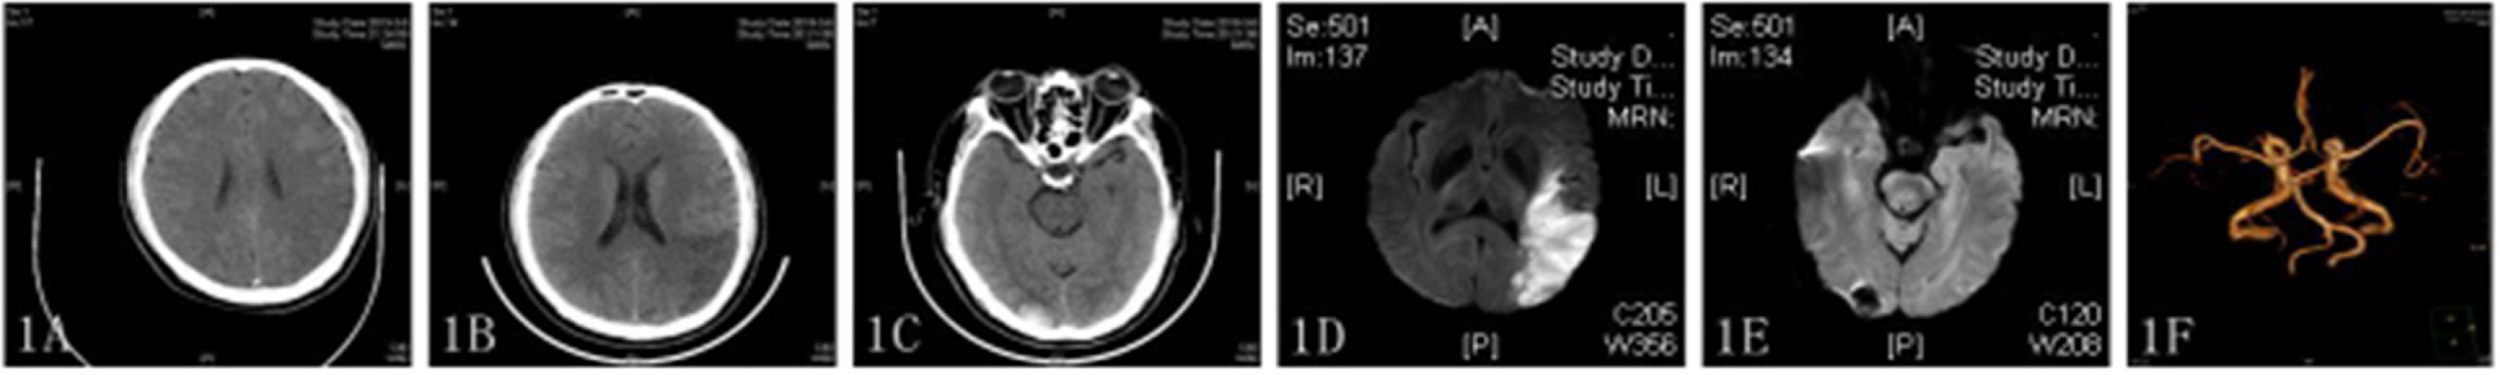

Three months later on March 5, 2019 (2019/03/05), he experienced a sudden episode of dizziness, incoherent speech, and weakness of his right limb during rest. His vital signs were stable after admission, and electrocardiography (ECG) showed no atrial fibrillation. His National Institutes of Health Stroke Scale (NIHSS) score was 6. The results of first and subsequent coagulation function tests are shown in Table 1, and accompanying inflammatory indicators (CRP) are shown in Table 2. Head CT showed an ambiguous boundary between gray and white matter in the left parietal lobe (Figure 1A), and chest CT showed changes in the area of gastric tumor resection – namely, multiple enlarged lymph nodes near the descending aorta. Other blood biochemical indices were normal. The patient was treated by IVT with 0.6 mg/kg rtPA 156 min after symptom onset. By the end of thrombolysis, the right limb weakness had improved, with an NIHSS score of 4; 24 h after thrombolysis (2019/03/06), CT showed multiple infarction in the left parietal lobe and multiple blood foci in the right occipital lobe (Figures 1B,C). At this time, the patient did not have obvious discomfort, and the dizziness and speech symptoms were slightly improved. Magnetic resonance imaging (MRI) performed on the 3rd day after thrombolysis (2019/03/07) revealed a large infarction area in the left temporoparietal lobe and hemorrhage in bilateral occipital lobes and the left cerebellar hemisphere (Figures 1D,E). A second coagulation function test was performed. Enhanced MRI showed that there was no tumor metastasis in the brain, and no atrial fibrillation or other arrhythmias were observed upon ECG examination. No thrombus was found by CT angiography (Figure 1F), and no obvious plaques were detected in the neck and lower extremities by color Doppler ultrasound. The patient has both cerebral infarction and cerebral hemorrhage, considering that antiplatelet drugs can aggravate the risk of bleeding, so he did not have antiplatelet treatment during the first hospitalization. The patient’s blood was hypercoagulable, suggesting cerebral embolism; however, a series of tests did not reveal the location of the thrombus. Therefore, a diagnosis of TS with advanced gastric cancer was made. The symptoms of dizziness and speech incoherence improved (NIHSS score of 4), and the patient was discharged from the hospital.

Figure 1. (A–C) CT image showing an indistinct gray matter boundary of the left frontal gyrus (A); a large, low-density shadow in the left parietal occipital lobe (B); and multiple high-density shadows on both sides of the occipital lobe (C). (D,E) Diffusion-weighted imaging (DWI) showing a high-intensity signal in the left frontoparietal–temporal–occipital artery island (D) and low-intensity signal in the left cerebellar hemisphere (E). (F) CT angiography showed no stenosis or occlusion.